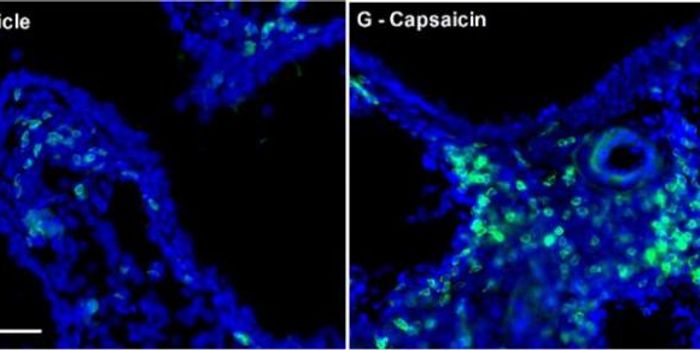

JUN 26, 2015NeuroscienceWhile asthma medications that suppress inflammatory signaling by immune cells or dilate airways are effective, they can ...